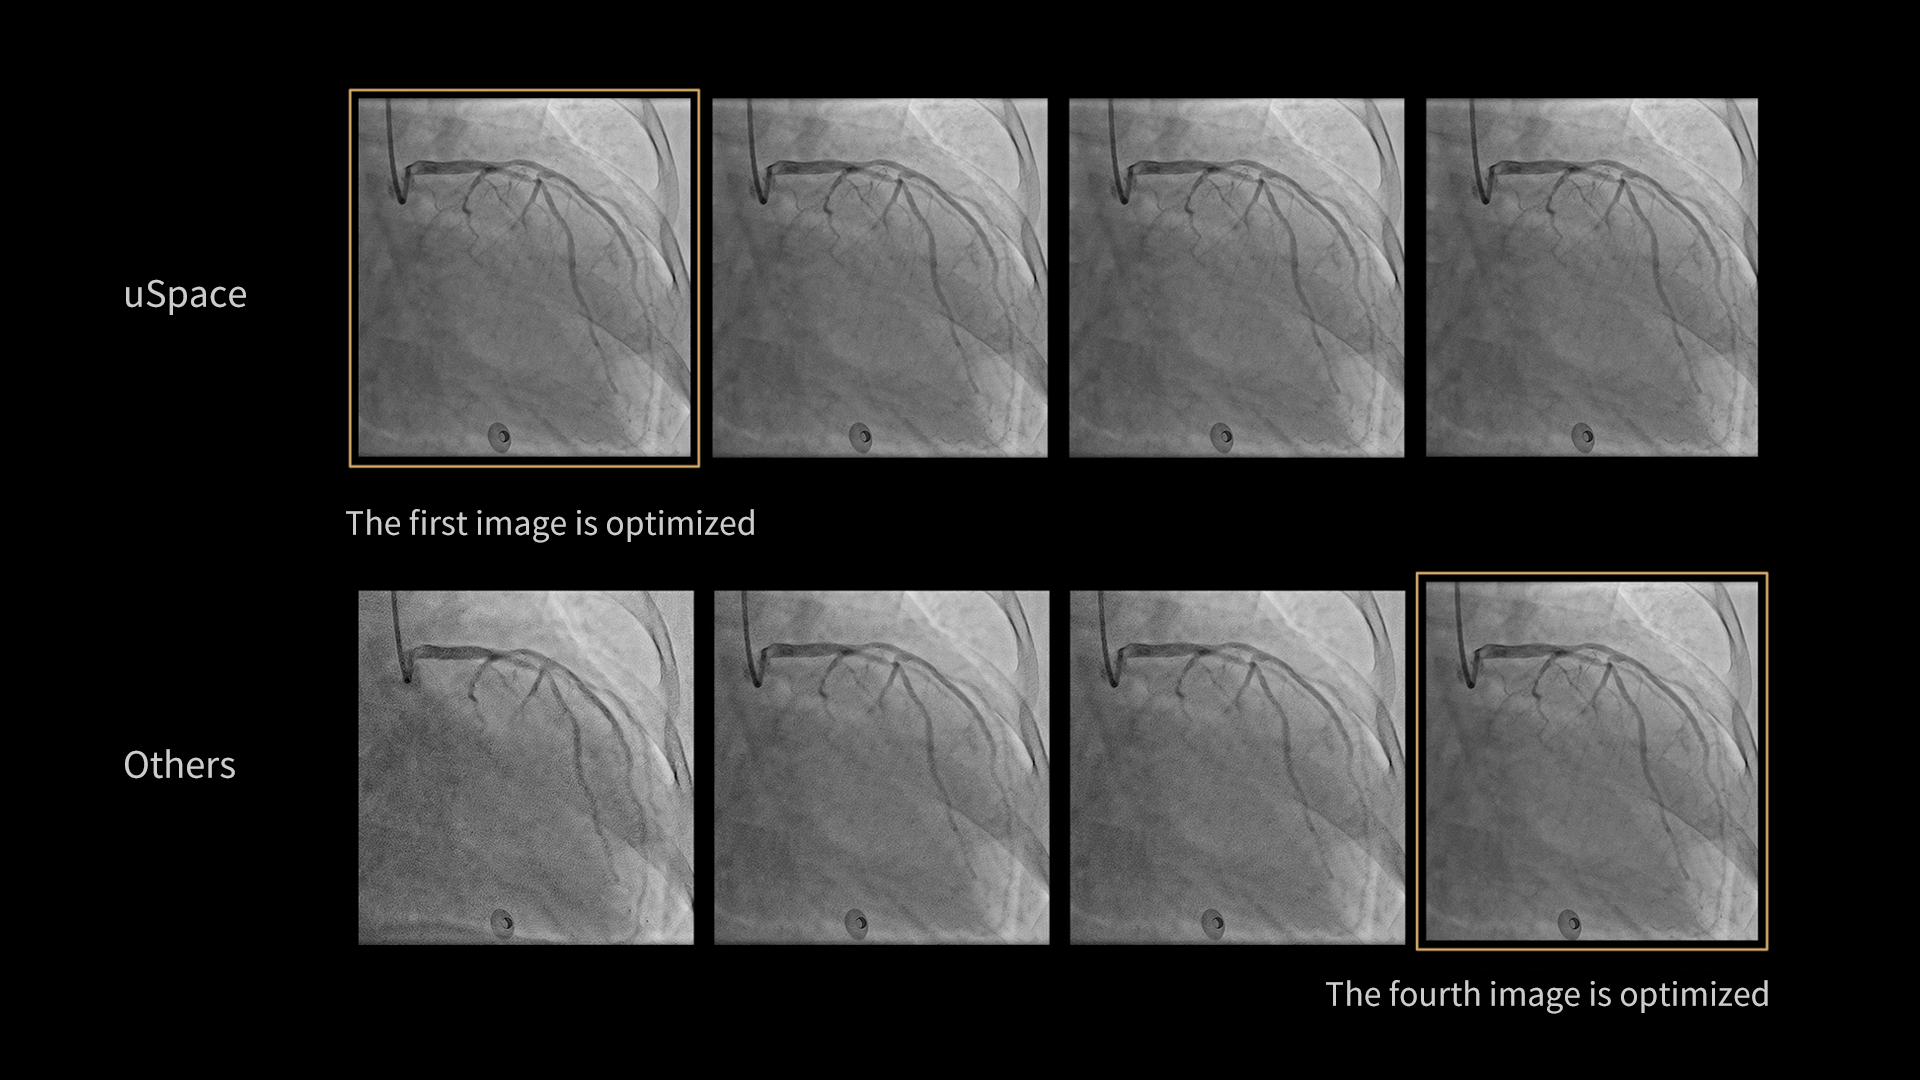

Imagistică inteligentă

Tehnologia uVera IQ abordează provocarea echilibrului dintre doza redusă de radiație și calitatea înaltă a imaginii, minimizând totodată cantitatea de substanță de contrast. Oferă imagini precise și clare, protejând în același timp echipa medicală și pacienții.

Îmbunătățire coronariană asistată de AI*

Funcția AI-Enabled Coronary Enhancement oferă imagini clare și consistente, permițând o reducere de până la 50% a dozei de substanță de contrast. Astfel, scade semnificativ riscul de CI-AKI (leziune renală acută indusă de contrast), fără a compromite acuratețea diagnostică.